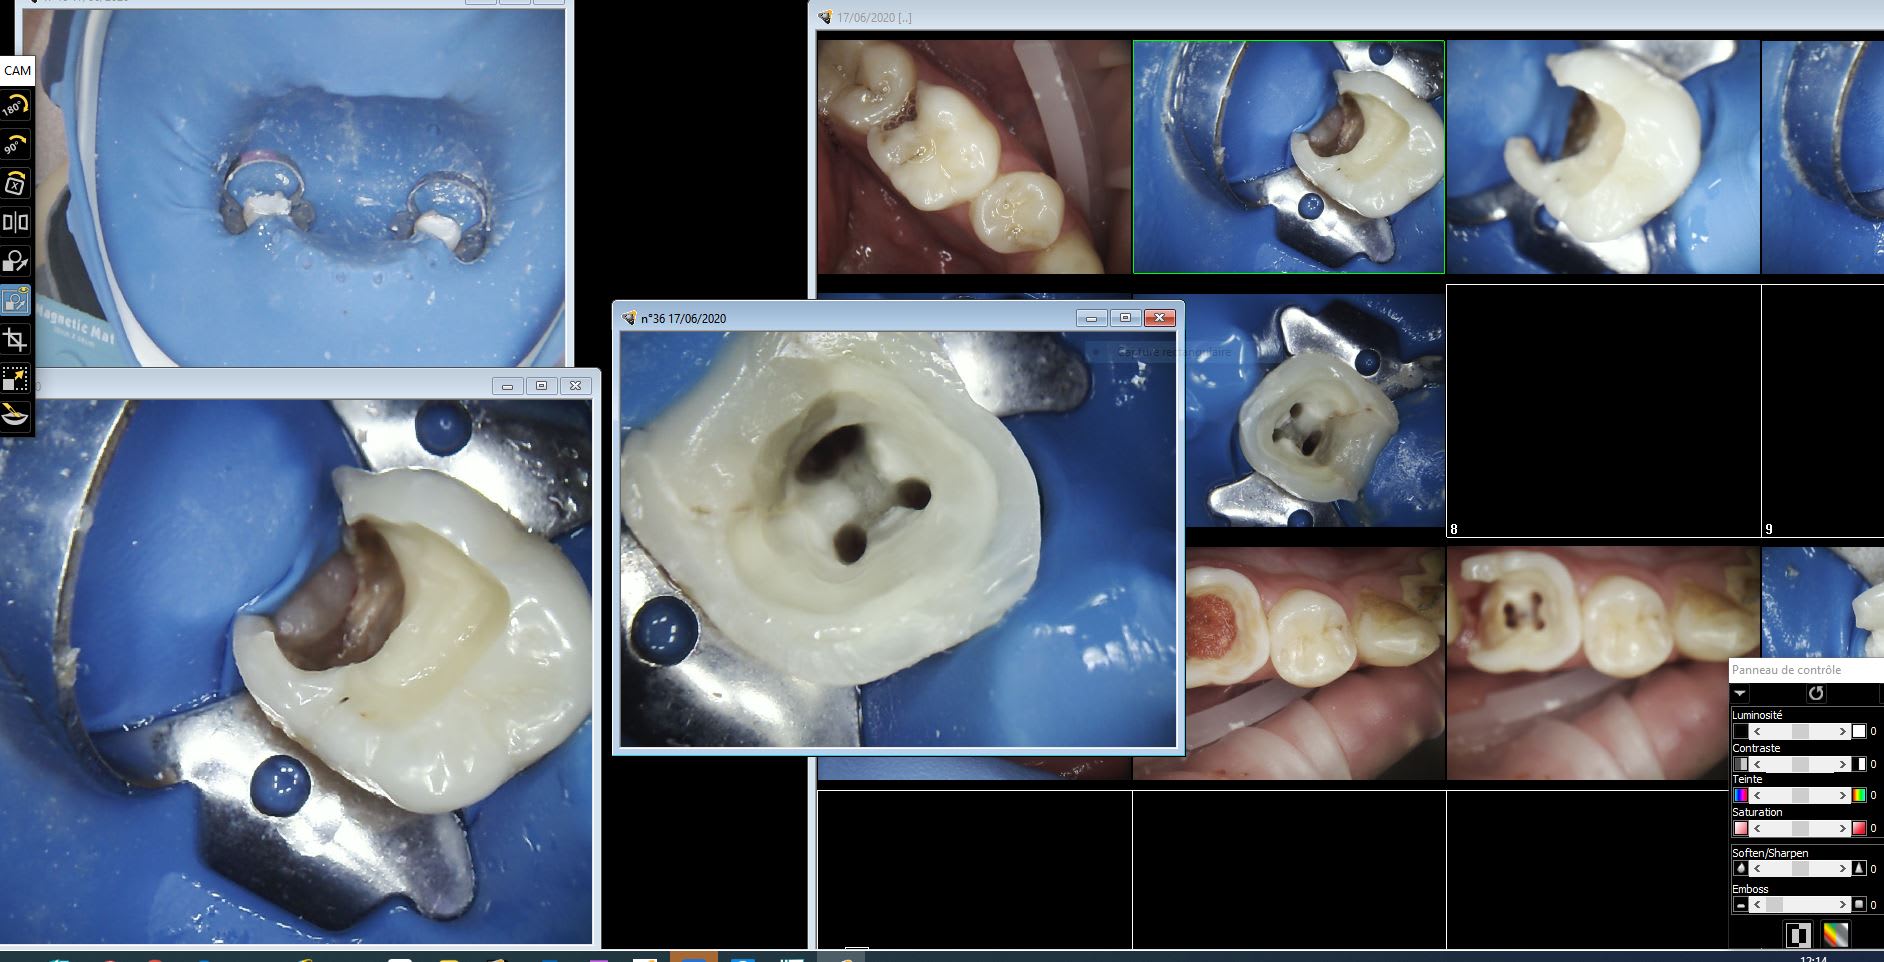

17/06/2020 à 12h20

Eviction gingivale 400, RCPE 600. J'ai bon Yobi ?

Rcpe 36 c5n473 - Eugenol